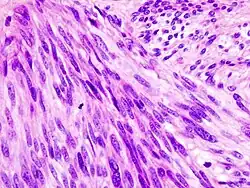

Histopathologic image of gastrointestinal stromal tumor of the stomach. Hematoxylin-eosin stain.

The definitive diagnosis is made with a biopsy, which can be obtained endoscopically, percutaneously with CT or ultrasound guidance or at the time of surgery. A biopsy sample will be investigated under the microscope by a pathologist physician. The pathologist examines the histopathology to identify the characteristics of GISTs (spindle cells in 70-80%, epitheloid aspect in 20-30%). Smaller tumors can usually be confined to the muscularis propria layer of the intestinal wall. Large ones grow, mainly outward, from the bowel wall until the point where they outstrip their blood supply and necrose (die) on the inside, forming a cavity that may eventually come to communicate with the bowel lumen.